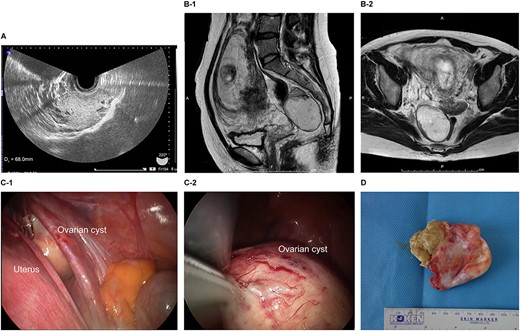

The patient was a 29-year-old, gravida 1, para 0 woman with no familial or medical history. She conceived naturally and was diagnosed a left ovarian cyst at 7 weeks of gestation by another doctor. She was referred to our hospital for further examination and operation. TVUS revealed a fetus in the uterus and a mass 7 cm in diameter on the left ovary, which appeared to be a dermoid cyst. MRI revealed left ovarian cystic tumors with fat tissue. The laboratory values, including levels of tumor markers (e.g. CEA, CA-125, CA 19-9 and SCC) were within the normal limits. We performed single-port laparoscopic surgery at 15 weeks and 3 days gestation to remove the left ovarian cysts. The procedure was performed within 99 minutes, and there were no complications (Fig. 3).

Imaging studies and laparoscopic views and specimen photograph of case 3. (A) Transvaginal ultrasound image showing an ovarian cyst. (B-1) Sagittal T2-weighted MRI showing an ovarian cyst. (B-2) Axial T2-weighted MRI showing an ovarian cyst. (C-1) Gestational uterus: ovarian cyst was moved from the pouch of Douglas. (C-2) Ovarian cyst was moved and located on the gestational uterus. (D) Ovarian Cyst.